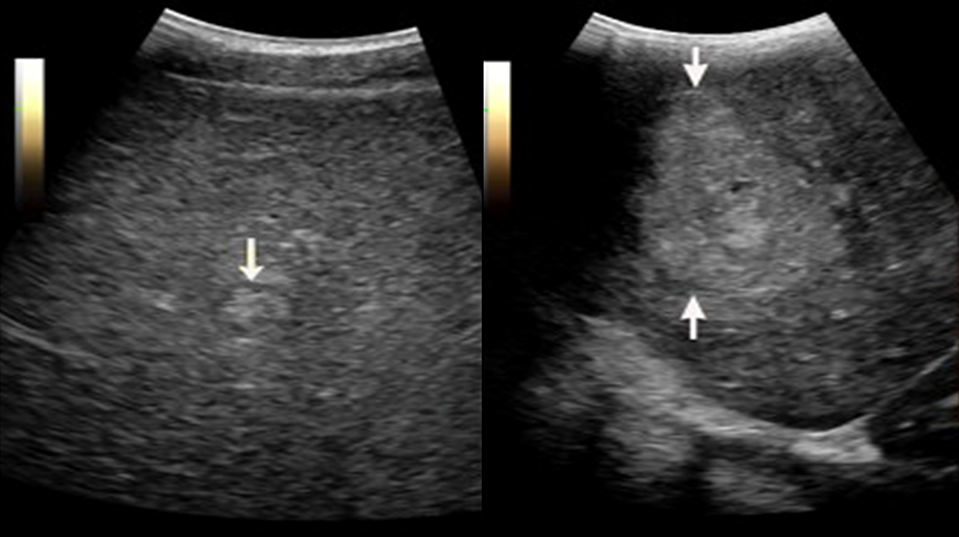

In conventional US guidance, some liver tumours have low conspicuity or are nearly undetectable when imaging small lesions or tumours located in challenging regions, such as the liver dome (see Figure 9). In addition, tumour mimics, such as regenerative nodules and prior ablation sites, may cause further confusion, making it even more challenging for physicians to accurately identify the tumour, as shown in Figure 10.

Invisible tumour 1

Figure 9. Left: invisible tumour in US; Right: visible tumour in MRI

Invisible tumour 2

Figure 10. Left: benign regenerative nodule; Right: malignant HCC